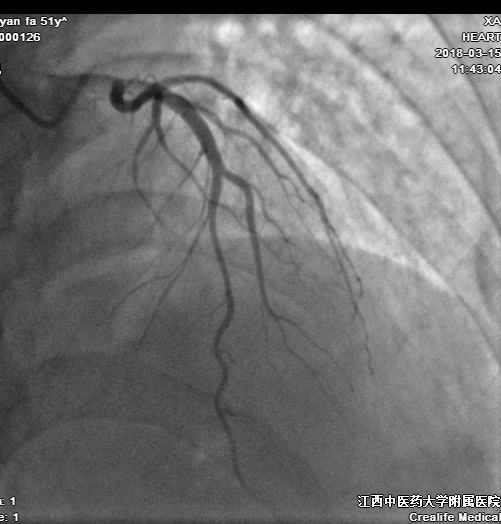

冠状动脉粥样硬化性心脏病

动脉粥样硬化